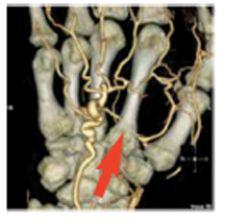

Significant advances have also been achieved in segmentation technologies, which allow clinicians to remove extraneous anatomy during review, but one of the more difficult segmentation challenges is separating small arteries from bone – for example, the deep palmar arch – and isolating this artery using traditional 3-D workstation software tools.

Barco just received FDA 510(k) clearance for CardiaMetrix, its clinical application suite for structural and functional analysis of contrast-enhanced cardiac studies. Integrated into PACS with Voxar 3D and VesselMetrix, a clinical application for quantitative vessel analysis of CTA and MRA, CardiaMetrix’s segmentation and bone removal software is designed to allow users to extract small vessels quickly and provides a 4-D cardiac analysis tool to produce 4-D movies of the beating heart with cardiac contours. The 4-D cine rapidly generates short axis, two-, three- and four-chamber long axis views, semi-automatic alignment with cardiac long axis position and automatic transfer of long axis position in end-diastolic and systolic phases to cardiac (LV) analysis.